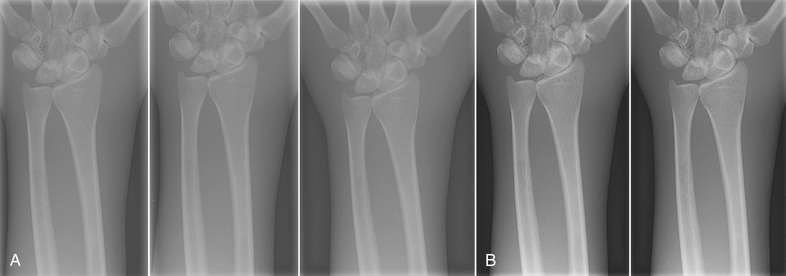

When the chest radiograph is digital, each region of the image (Figure 21-12A) can be represented by the frequency distribution of the digital values of each pixel, as shown in Figure 21-12B. The location of those image regions on the digital image receptor response curve is shown in Figure 21-12C. The relative shape of this histogram is characteristic of all posteroanterior (PA) chest digital radiographs.

Even more important is the fact that the shape of an image histogram is characteristic of each anatomical projection. Figure 21-13 shows the characteristic shapes of image histograms of additional radiographic projections.

Most digital radiographic imaging systems have the ability to store and analyze characteristic image histograms for each radiographic projection. By storing 50 PA chest image histograms and averaging the value of each frequency interval, a representative histogram is produced for each image receptor. The histogram can be regularly updated from newer images.

This places an additional responsibility on the radiographer. In addition to selecting technique, the radiographer must engage the appropriate histogram before examination so as to apply the appropriate reconstruction algorithm to the final image (Figure 21-14).